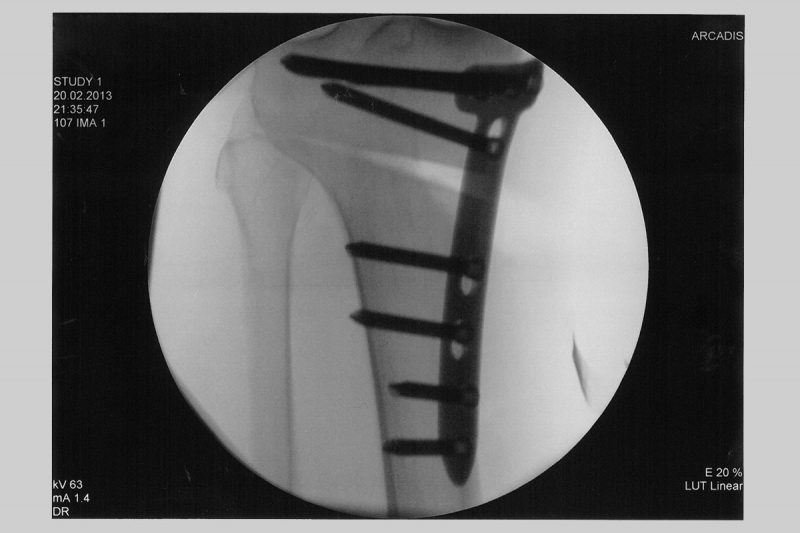

Knee Realignment Osteotomies Dr A. Theodorides Knee Surgeon. Eintrag von am 04.10.2020 - Anzahl gelesen : 1 Sehr kurzer Erfahrungsbericht Umstellungsosteotomie 0, Ich bin 43 Jahre alt, habe Gonarthrose in beiden Knieen, angeblich Grad 2 (-3) Nun hat er mir empfohlen eine Umstellungsosteotomie zu machen da wird ein Knochenkeil raus gesägt und an einer anderen Stelle eingesetzt einschließlich Platten, damit die Achse dann wieder grade ist.